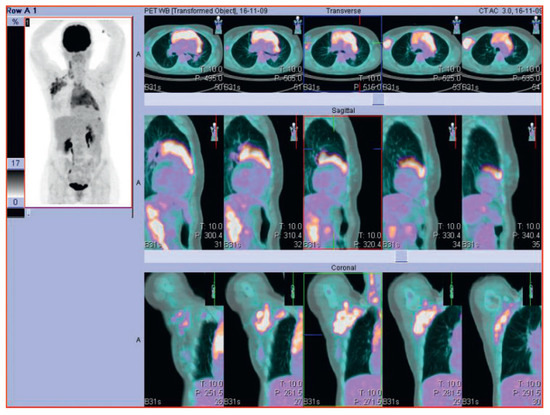

Der 70-jährige Patient wurde uns zugewiesen zur stationären kardialen Rehabilitation bei St. n. mechanischem Aortenklappenersatz wegen schwerer degenerativer Aortenstenose.[...]